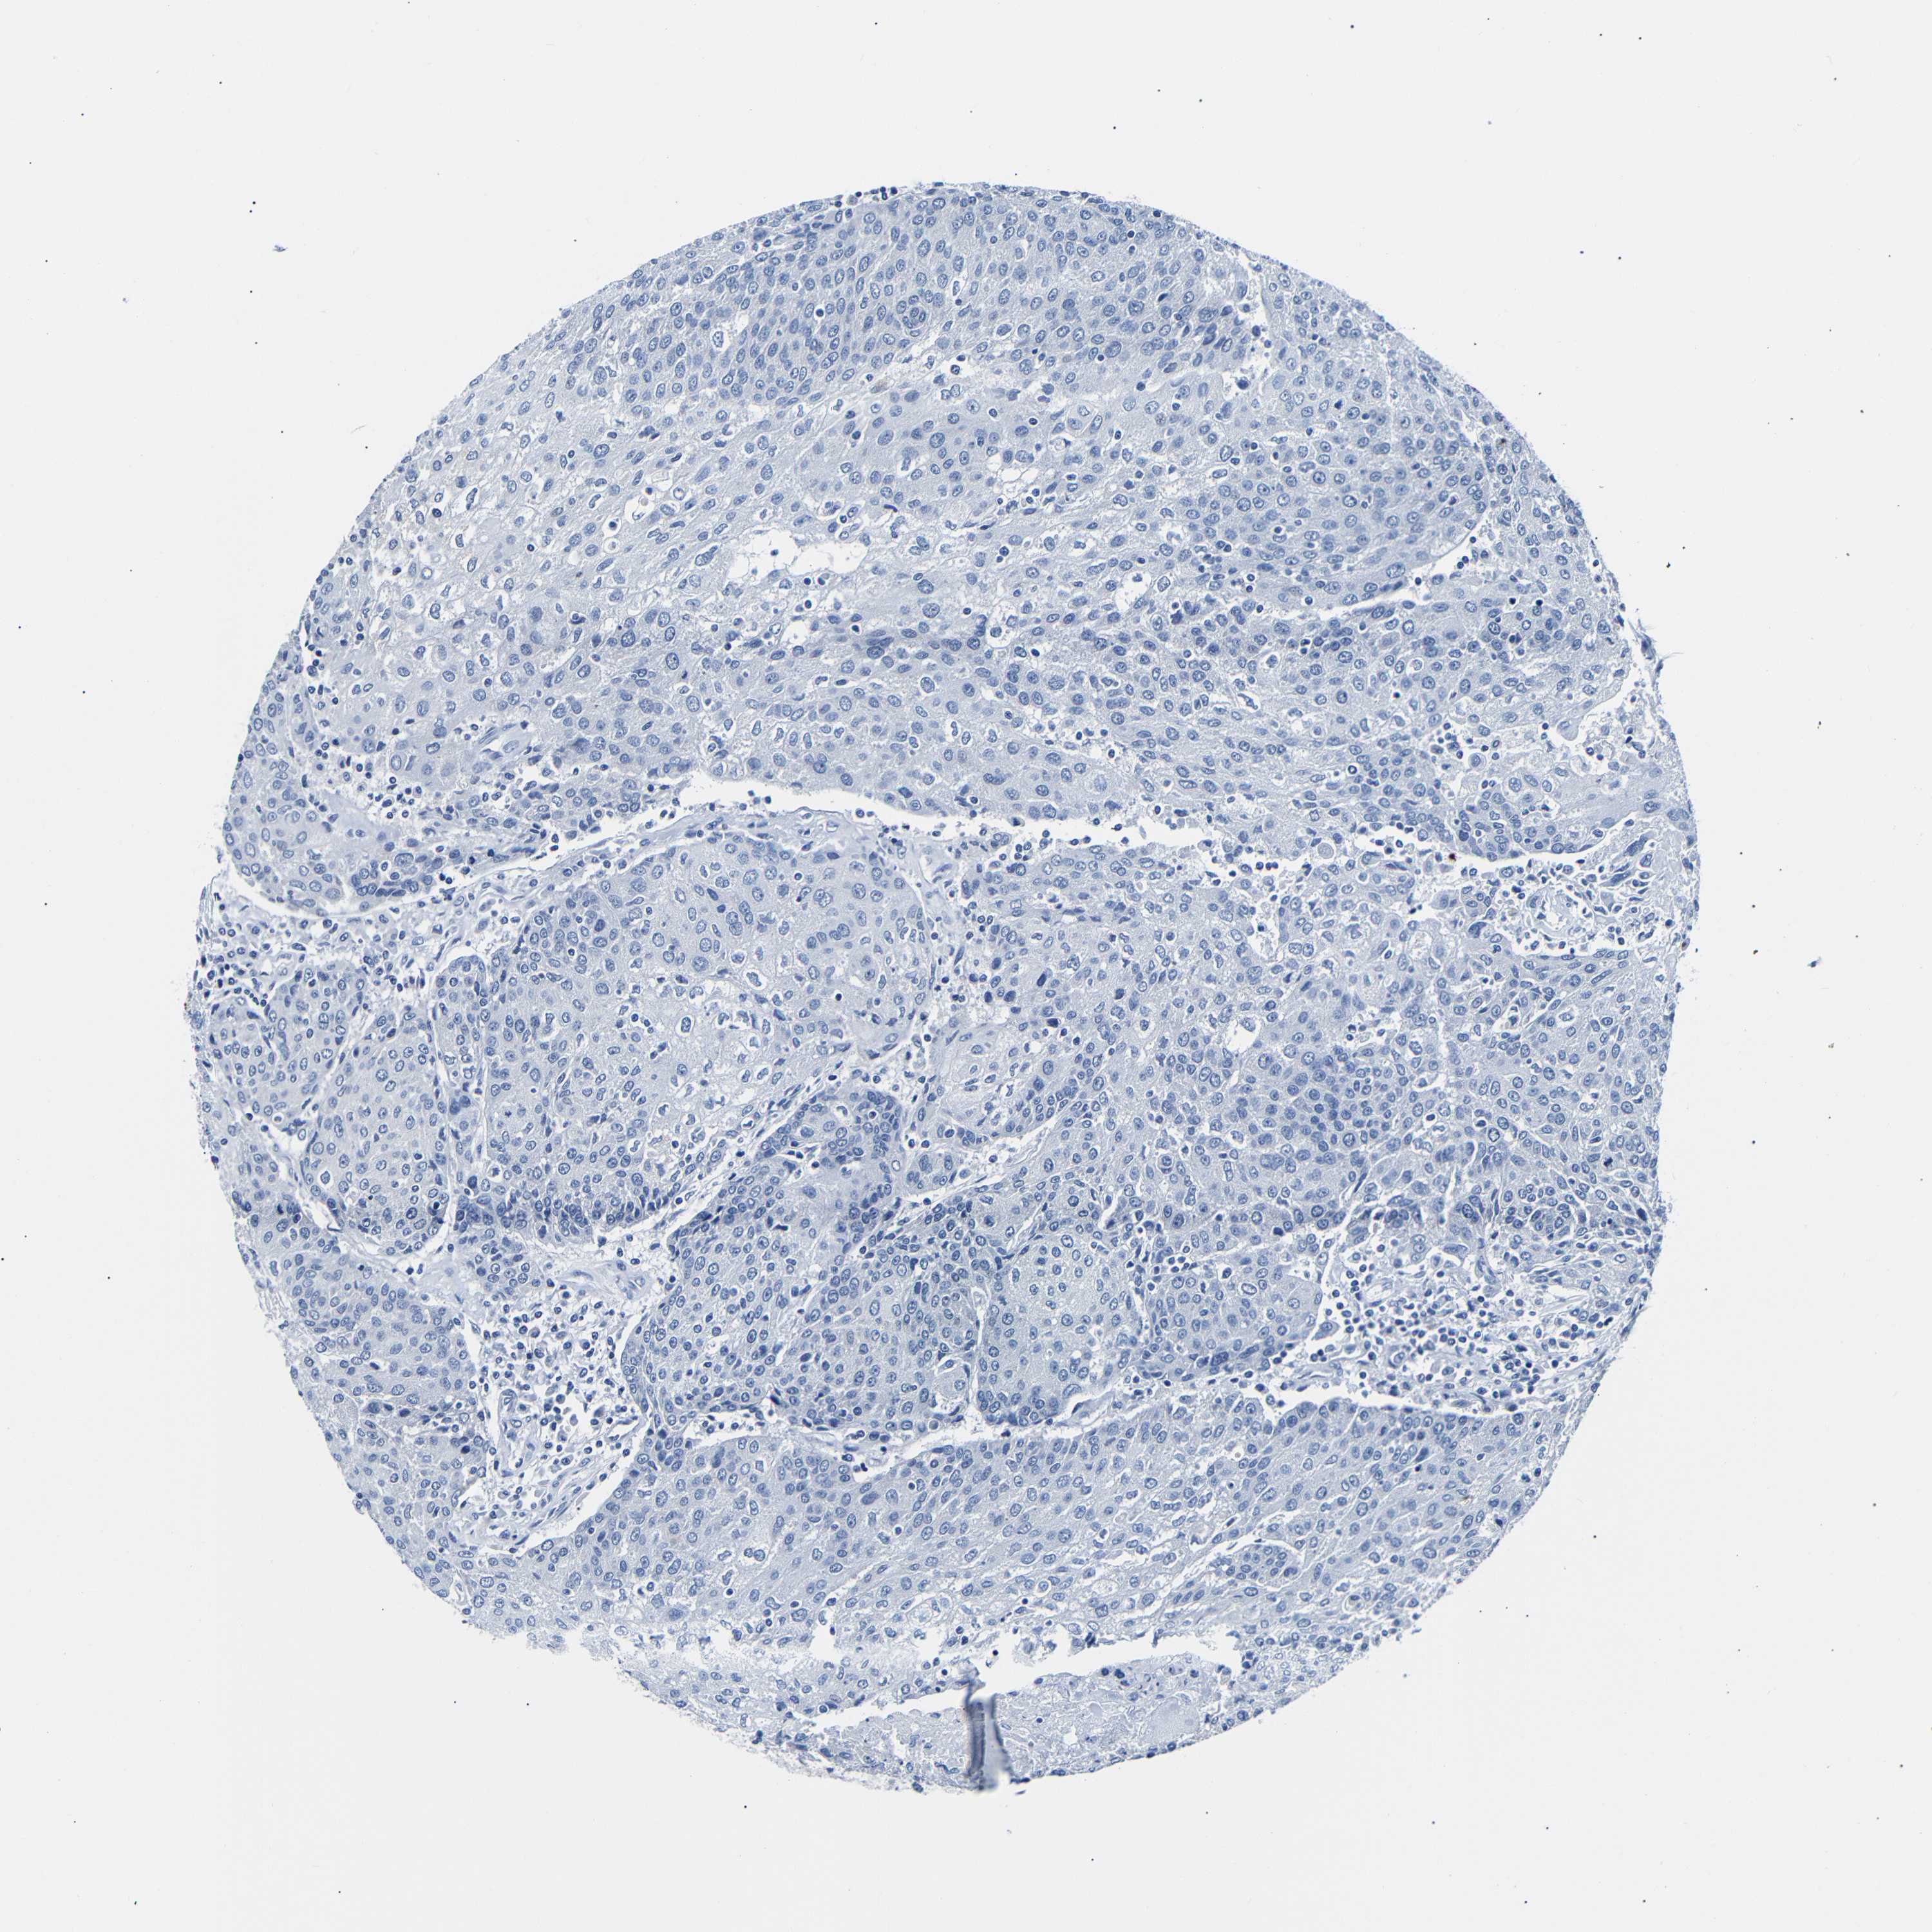

UROTHELIAL CANCER - Protein expressioni

A mouse-over function shows sample information and annotation data. Click on an image to view it in a full screen mode. Samples can be filtered based on level of antibody staining by selecting one or several of the following categories: high, medium, low and not detected. The assay and annotation is described here.

Note that samples used for immunohistochemistry by the Human Protein Atlas do not correspond to samples in the TCGA dataset.

Antibody stainingi

Antibody staining in the annotated cell types in the current human tissue is reported as not detected, low, medium, or high, based on conventional immunohistochemistry profiling in selected tissues. This score is based on the combination of the staining intensity and fraction of stained cells.

Each image is clickable and will lead to virtual microscopy that enables deeper exploration of all samples and also displays staining intensity scores, fraction scores and subcellular localization as well as patient and tissue information for each sample.

Antibody HPA013392

Antibody HPA015600

Antibody CAB004417

Staining

High

Medium

Low

Not detected

Intensity

Strong

Moderate

Weak

Negative

Quantity

>75%

75%-25%

<25%

None

Location

Nuclear

Cytoplasmic/membranous

Cytoplasmic/membranous,nuclear

Urothelial carcinoma, Low grade

Urothelial carcinoma, High grade